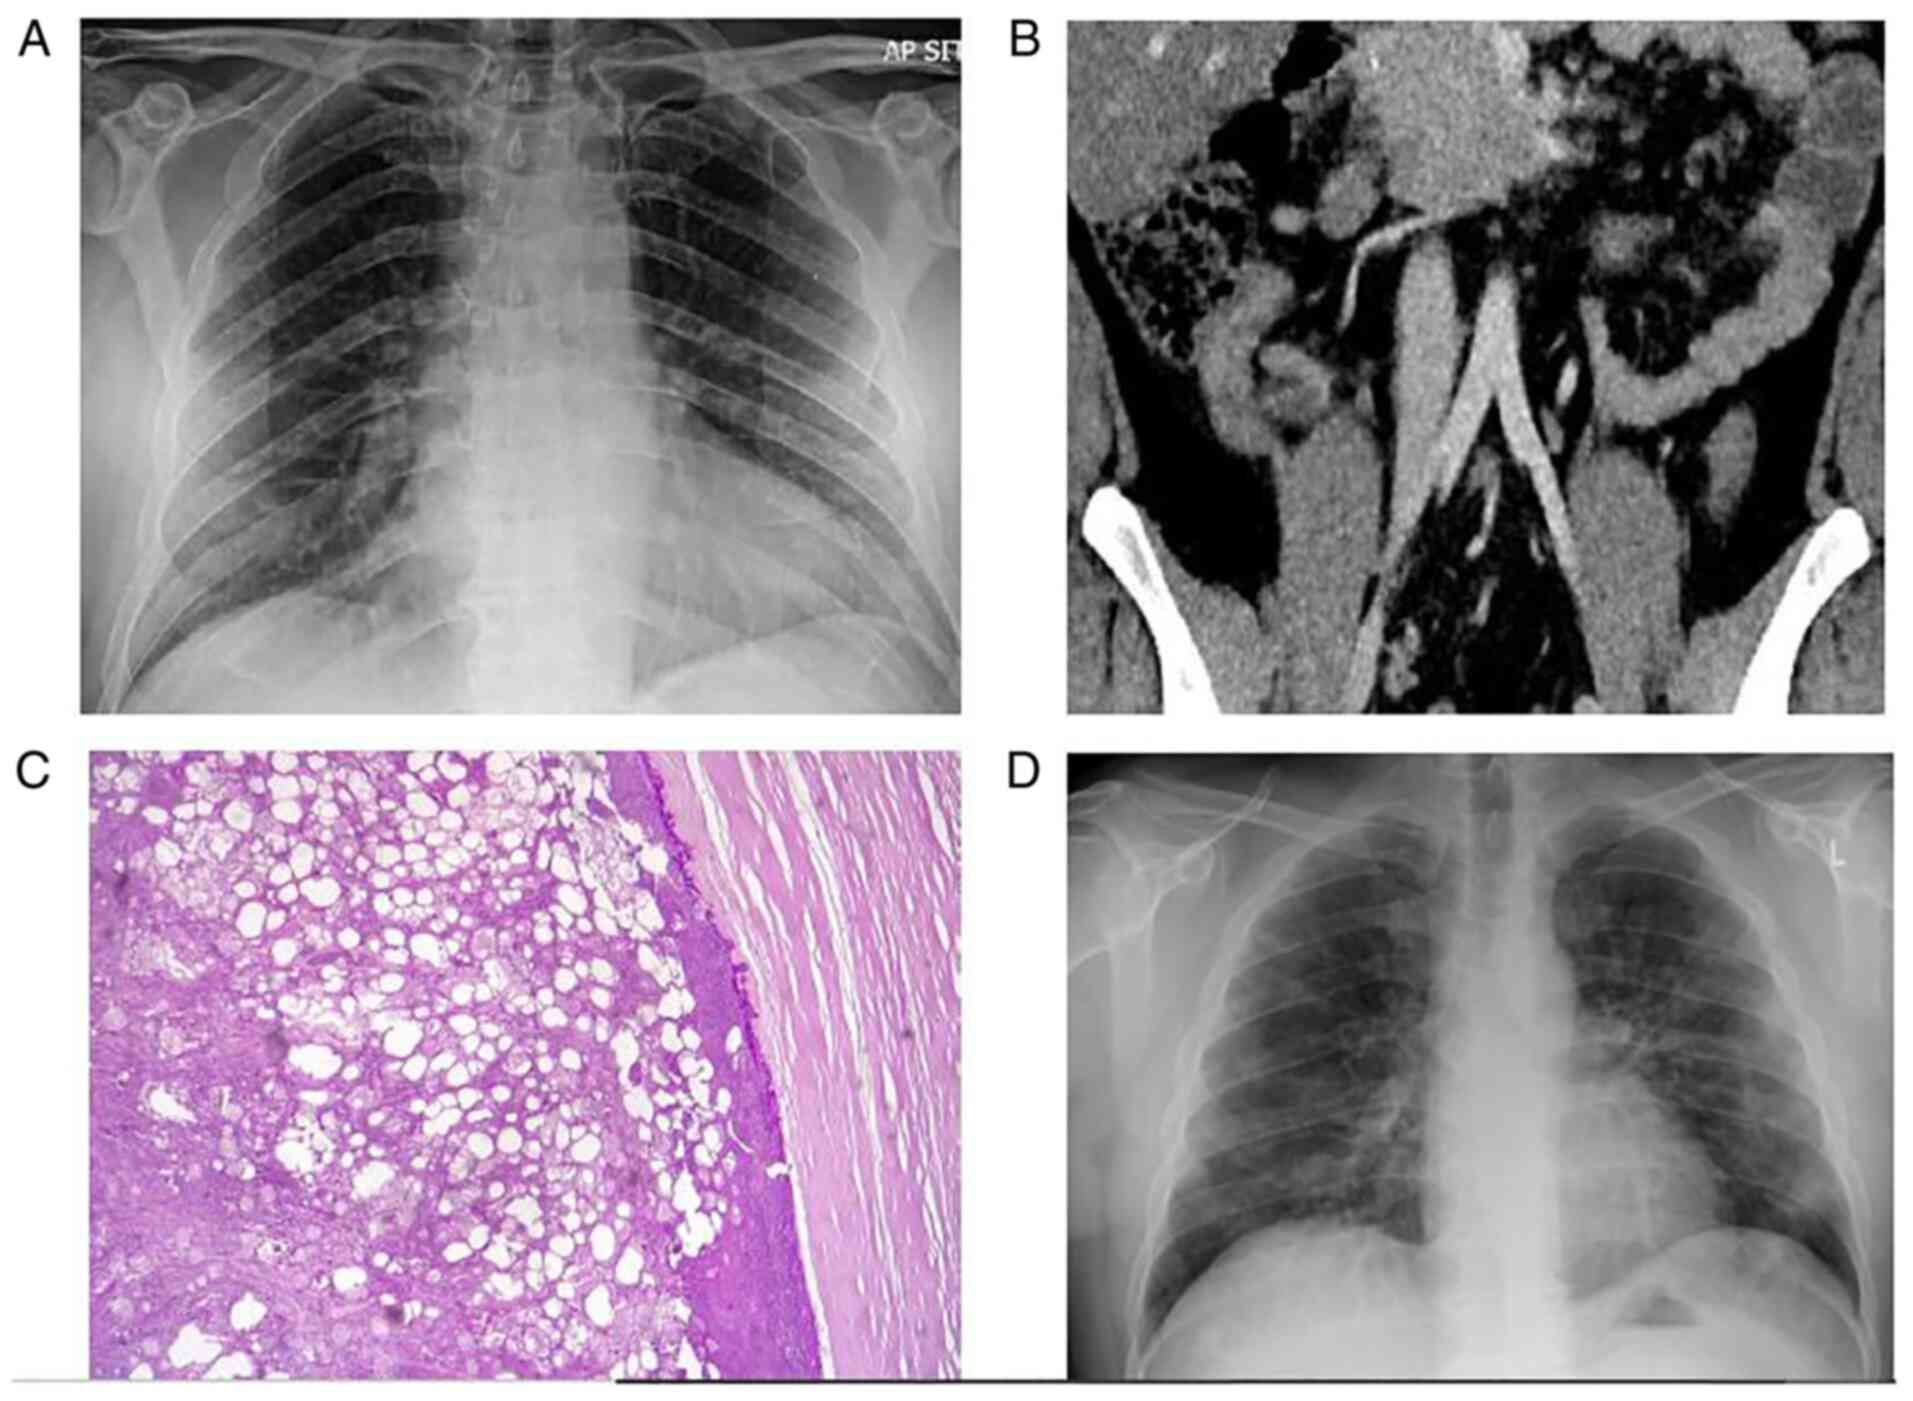

Figure 4

Case 4. (A) Normal chest X-ray. (B) An abdominal computed tomography revealed an inflamed appendix originating from the cecum in deep pelvic position. (C) Hematoxylin and eosin staining; original magnification, x400. The histological analysis revealed acute appendicitis with intense neutropilic infiltration of the appendix wall.

A chest X-ray was performed, which was normal (Fig. 4A). The Alvarado total score was 7 out of 10 based on the symptoms and laboratory tests. The patient had probable appendicitis according to the Alvarado score. He underwent an abdominal CT scan, which revealed an inflamed appendix originating from the cecum in deep pelvic position (Fig. 4B). An RT-PCR test for COVID-19 was conducted and the result was positive. With all COVID-19 precautions taken, an open appendectomy was conducted under general anesthesia. The histopathological examination of appendicular tissue revealed acute appendicitis with intense neutropilic infiltration of the appendix wall (Fig. 4C).

A chest X-ray was performed, which was normal (Fig. 5A). The Alvarado total score was 8 out of 10 based on the symptoms and laboratory tests. The patient had probable appendicitis according to the Alvarado score. The patient underwent an abdominal CT scan, which revealed an appendiceal enlargement with intraluminal calcified fecalith and marked inflammatory changes in the surrounding mesenteric fat with possible microperforation (Fig. 5B). An RT-PCR test for COVID-19 was conducted and the result was positive. With all COVID-19 precautions taken, a laparoscopic appendectomy was conducted under general anesthesia. The histopathological examination of appendicular tissue revealed acute gangrenous appendicitis (Fig. 5C).

Figure 5

Case 5. (A) Normal chest X-ray. (B) An abdominal computed tomography revealed an appendiceal enlargement with intraluminal calcified fecalith and marked inflammatory changes in the surrounding mesenteric fat with possible microperforation. (C) Hematoxylin and eosin staining; original magnification, x200. The histological analysis revealed acute gangrenous appendicitis.